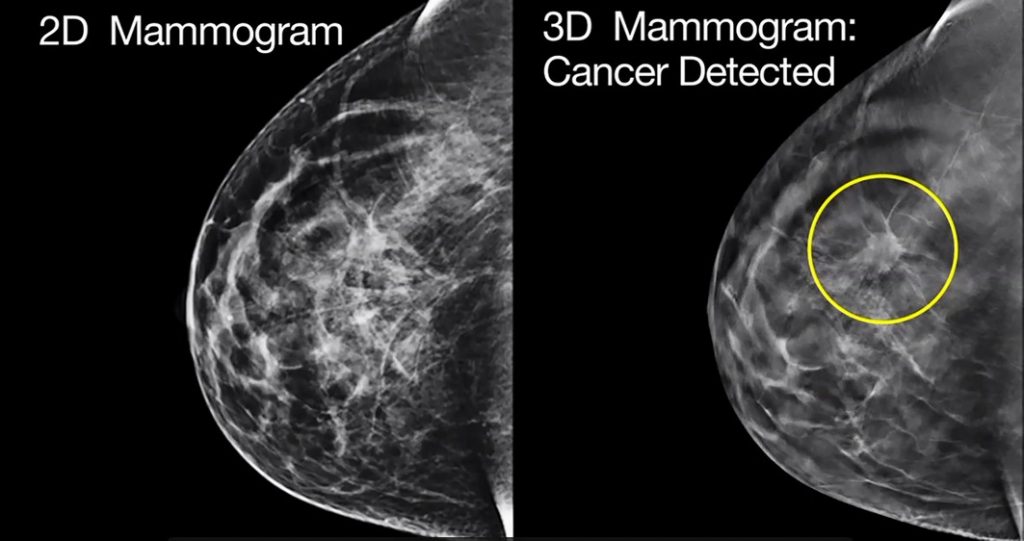

ปัจจุบัน การตรวจแมมโมแกรมเป็นเป็นวิธีตรวจคัดกรองมะเร็งเต้านม ที่วงการแพทย์ยอมรับว่ามีประสิทธิภาพมากที่สุดในปัจจุบัน เพราะสามารถตรวจหาก้อนมะเร็งได้ตั้งแต่มีขนาดเล็กเพียง 2 มิลลิเมตร ซึ่งเป็นระยะเริ่มแรกของโรคที่ร่างกายมักไม่แสดงความผิดปกติใด ๆ